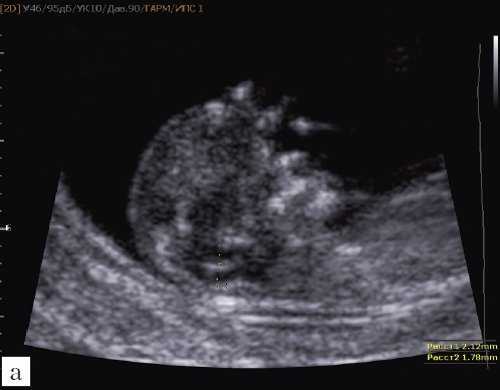

Так как речь идет о сроках первого скрининга, т.е. раннего осмотра, новый ультразвуковой маркер мы назвали "осьминожкой" (рис. 3).

а) Стрелками указана голова "осьминожки" - диэнцефалон (таламус).

б) Красный цвет - диэнцефалон (таламус), со стволом мозга (верхняя ножка) и IV желудочком (нижняя ножка); желтый цвет - большая цистерна головного мозга; синий цвет - воротниковое пространство.